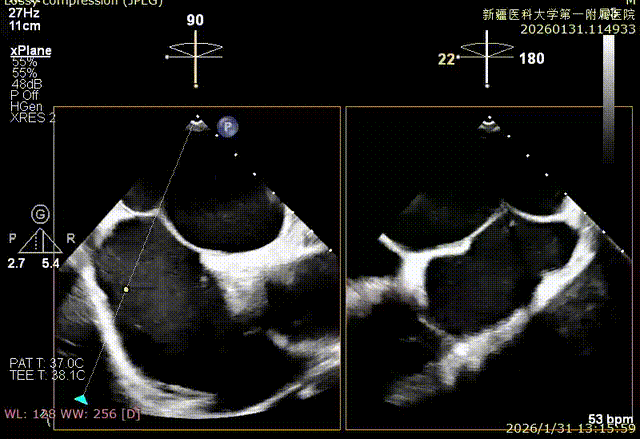

XPLAN切面2区后叶栓系

XPLAN切面中重度反流

3D enface 切面

3D enface观察反流